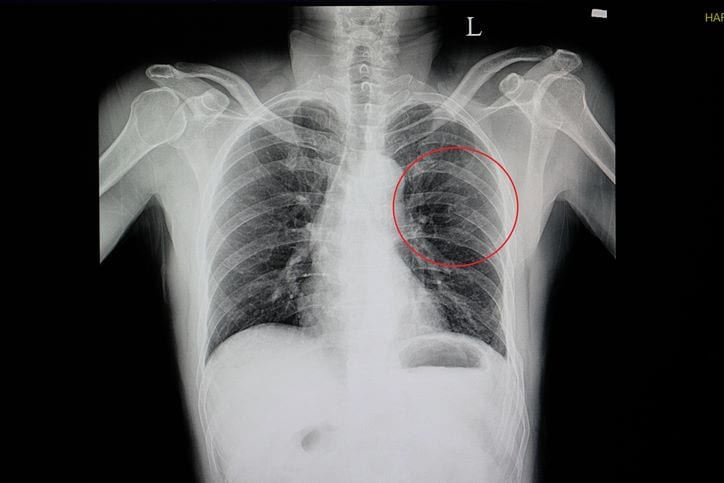

If you suspect you have broken ribs after a car accident, seeking immediate medical attention is crucial. Even if the pain seems manageable initially, fractured ribs can worsen without proper treatment. A medical professional can assess the extent of your injuries through physical examination and imaging tests such as X-rays or CT scans.

A healthcare professional can perform diagnostic tests, such as X-rays, to confirm the diagnosis and develop a treatment plan.